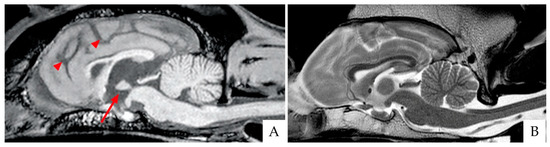

4.1. Brain Imaging